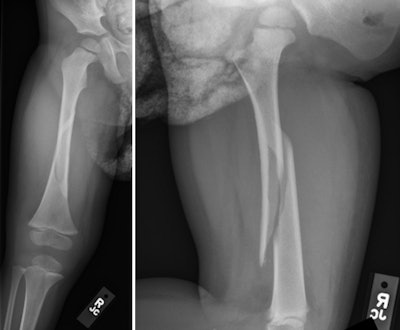

![]() |

| Fracture in normal bone. Anteroposterior (left) and lateral (right) radiographs of the right femur in a 2-year-old with no metabolic bone disease demonstrates an acute displaced spiral fracture through the femoral diaphysis. Note the normal appearance of the metaphyses and growth plates, as well as normal bone mineralization. All images courtesy of Seattle Children's Hospital. |